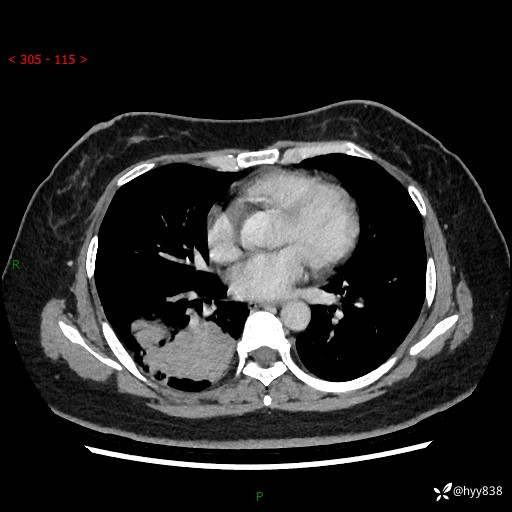

增强动脉期+静脉期